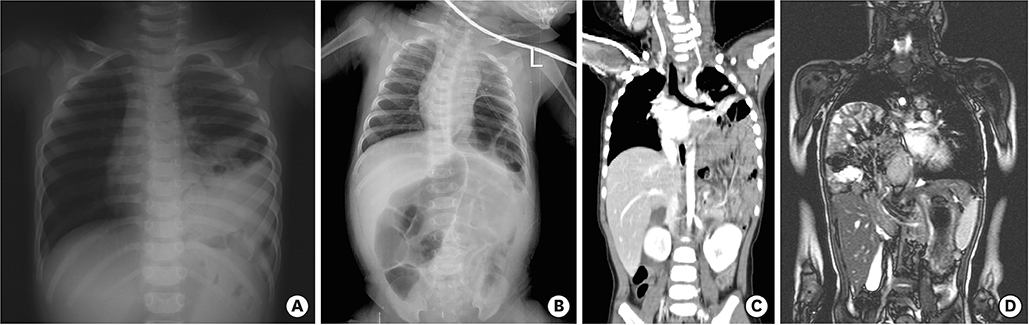

Fig. 1

Initial chest X-rays and convincing secondary additional imaging studies of late presenting CDH in children. (A) Initial chest X-ray of the left side CDH which was vague. (B) Chest X-ray after a gavage tube insertion in the left side CDH. (C) Chest CT showing the left side CDH. (D) Chest MRI showing the right side CDH.

CDH, congenital diaphragmatic hernia; CT, computed tomography; MRI, magnetic resonance imaging.

As shown in Table 1, the range of patients’ age at diagnosis was scattered insignificantly from 55 days to 13 years. The ratio of sex (male:female) was 2:1. The clinical manifestations of the patients were not typical nor single but mixed or various. The most common symptom was vomiting, followed by abdominal pain, chest discomfort, dyspnea, and cyanosis. As an initial diagnostic imaging study, chest X-ray was performed routinely in all patients, of whom one patient checked it after the insertion of a gavage tube fortunately. As a secondary additional imaging study, chest computed tomography (CT) was performed in four patients, abdominal ultrasonography was performed in 2 patients, and chest magnetic resonance imaging (MRI), abdominopelvic CT, renal scan were each carried out for one patient. Fig. 1 shows initial chest X-ray and convincing secondary additional imaging studies for these patients. In operative findings, the location of the diaphragmatic defect was the left posterolateral side in 5 patients and the right posterior side in 1 patient. The small bowel and colon were herniated into the thoracic cavity through the diaphragmatic defect in all of the patients. Spleen herniation was identified in 3 patients. Stomach and kidney herniation were each identified in 2 patients. Malrotation of the cecum and Meckel's diverticulum were discovered incidentally during operation. Most of the operations were performed promptly after confirmation of diaphragmatic hernia; however, 1 patient with right posterior side CDH received preoperative care for acute bronchiolitis for 9 days. The postoperative outcomes were excellent without significant complications.